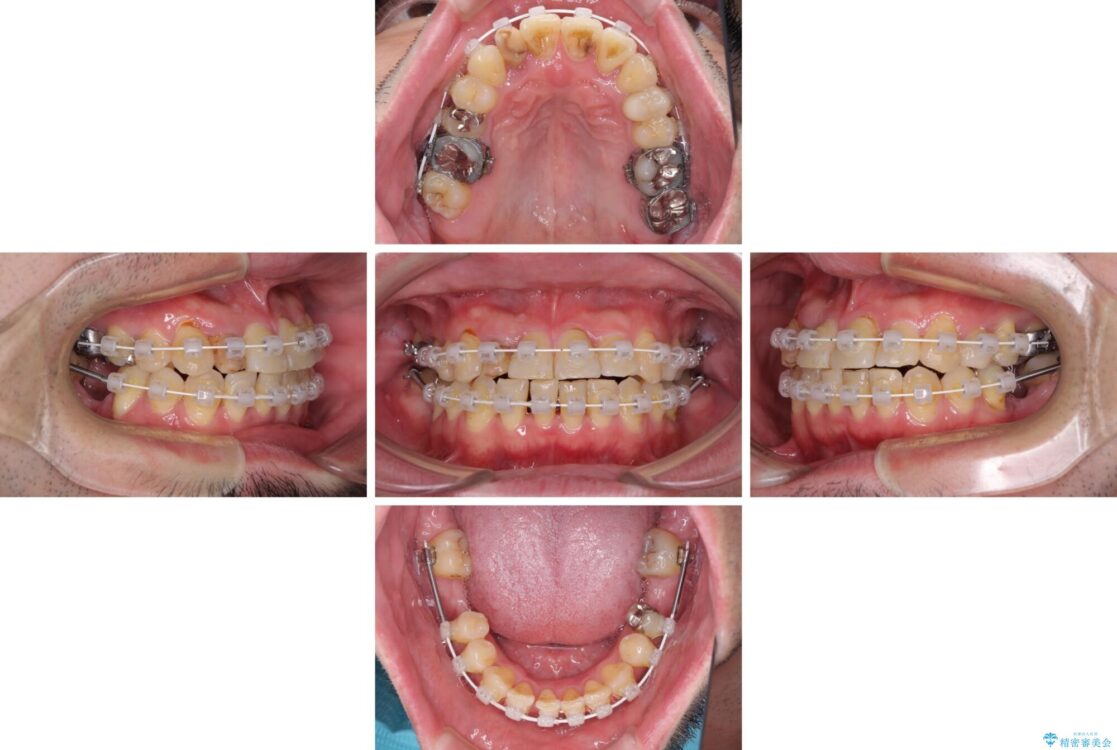

治療途中

• 割れてしまった奥歯とデコボコの前歯 矯正治療とインプラント治療 治療途中画像